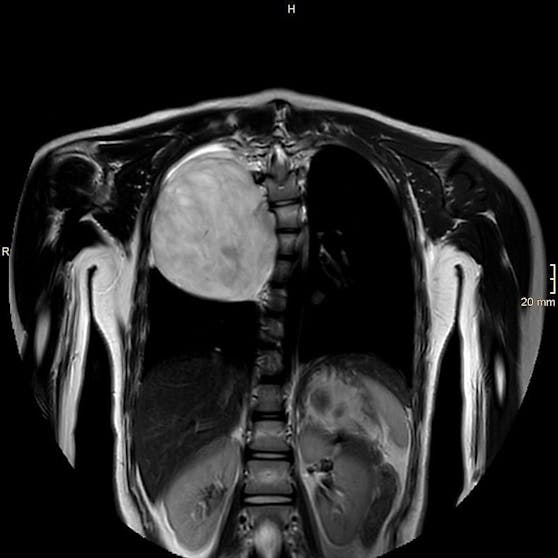

Nach der Flucht aus der Heimat wurde bei Sadaf bei einer Routineuntersuchung in Kärnten ein zehn Zentimeter großer Tumor festgestellt, der an der Wirbelsäule saß und bereits die Lunge verdrängte. Die Schülerin kam sofort zur weiteren Abklärung ins Eltern-Kind-Zentrum am Klinikum Klagenfurt. "Wir haben das Mädchen genau untersucht und konnten glücklicherweise feststellen, dass der Tumor lokal beschränkt und ohne Hinweis auf Bösartigkeit war", erzählt Jörg Jahnel, Abteilungsvorstand der Kinder- und Jugendheilkunde laut "Kleiner Zeitung".

Der Tumor wuchs von der Wirbelsäule aus in den Brustraum.

Kabeg

Basierend auf diesen Erkenntnissen, entschied das Team der Kinder- und Jugendchirurgie rund um Primarius Johannes Schalamon, eine OP durchzuführen. "Da das Gewächs eng an der Wirbelsäule lokalisiert war, zogen wir die Neurochirurgie hinzu", berichtet Schalamon, der den Eingriff am 21. März vornahm. "Es war ein sehr komplexer Fall. So etwas sehen wir sehr selten."

"Heute" auf Google als bevorzugte Quelle festlegen